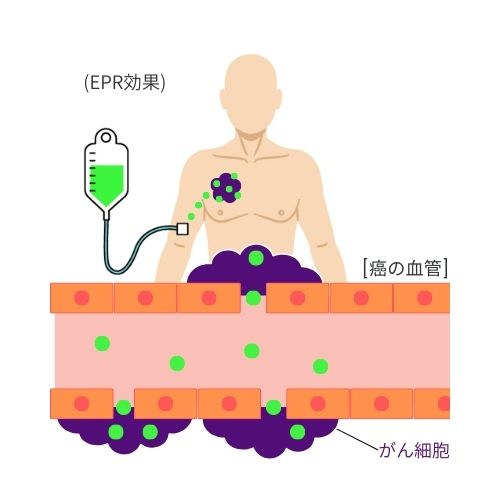

➁ 薬剤をがん細胞へ集積

正常な血管壁は整然としており緻密に構成されていますが、がん組織の血管壁はこれとは異なり、構造に乱れが見られます。この構造上の差異を利用して、薬剤を効率的にがん細胞に送り届けることができます。この方法は「EPR効果」として知られ、がん治療において重要な役割を果たしています。

がんの新生血管は不完全であり、新生血管内に約200nmの隙間が存在するのに対し、正常な細胞は6nm~7nm程度の隙間が存在します。

その為、約100nmのリポソーム化した薬剤は正常な細胞には取り込まれず、新生血管から腫瘍の組織内に運ばれ、蓄積します。

これらの血管壁差を利用し、癌細胞へ効率的に薬剤を運ぶ特性DDS(ドラッグデリバリーシステム)をEPR効果と呼びます。

この性質により、がん細胞へ選択的に薬剤を届けることができるため、正常細胞へのダメージが少ない利点があります。

正常な血管壁は乱れなく緻密な状態ですが、がんの血管壁は塑像(そぞう)な状態となっています。 がん細胞は酸素を含む栄養を得て成長するために血管を新生させます。新生血管は正常血管と比較して不完全であり、 血管内皮細胞間に約200nmの隙間が存在しています(正常な細胞の場合6~7nm程度)。 その為、薬剤(数百nmのナノ粒子)は正常な血管には取り込まれずに、腫瘍の組織へ運ばれます。 この血管壁差を利用したドラッグデリバリーシステムをEPR効果(ノーベル賞候補の熊本大学名誉教授である前田浩博士による技術)といい、薬剤をがん細胞に定着し、 光を照射する事でがん細胞を攻撃します。